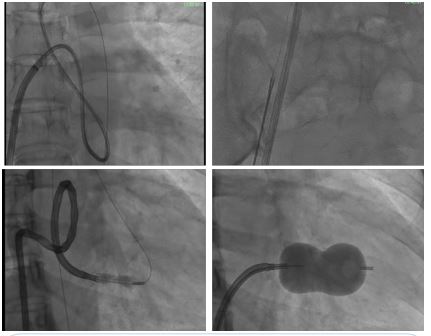

PTMC procedure was proceeded via femoral venous access through 8F sheath in right femoral vein and 6F Common Femoral Arterial (CFA) access. The 6 F pigtail catheter was positioned in non-coronary aortic sinus. The procedural steps were according to standard technique. The needle tip position was confirmed in antero-posterior view and lateral fluoroscopy views for septal puncture. The Accura balloon catheter was successfully parked in the left atrium. However, the further step of entry into LV was difficult. We tried the modified strategies for LV entry like loop technique and over wire technique, which failed. Thus we used the venous arterial loop technique as a bailout. The balloon was exchanged with Mullen’s sheath telescoped with JR diagnostic catheter. With help of support system, 0.25-inch Jtip 280 cm Terumo wire was negotiated across the mitral valve into LV (Figure 1A) and then antegradely through the aorta and managed to progress the wire tip position in right external iliac artery. Due to absence of snare, we used a rigid forceps to externalise the wire through the upsized 7F sheath placed in CFA (Figure 1B). The balloon could be then slide into LV over the veno-arterial rail (Figure 1C). The step wise balloon dilation went to a maximum volume of 26 cc (Figure 1D). Post procedure was uneventful and echocardiogram showed both the commissures of mitral valve got opened with valve area of 2.0 cm2 without significant mitral regurgitation.

Figure 1: Demonstration of Bail out technique for difficult left ventricle entry – the veno-arterial loop technique. (A) 0.25-inch guide wire successfully negotiated through the mitral and aortic valve supported by mullens sheath with JR catheter, (B) Guide wire was externalised with help of rigid forceps, (C) Accura balloon catheter negotiated over the veno-arterial loop across the mitral valve, (D) Step-wise dilation of balloon catheter across the mitral valve.